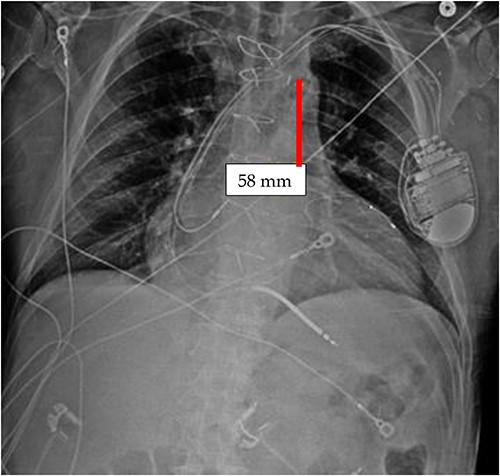

It appears that the IABP became mispositioned after its initial placement as seen on follow-up CXR (Fig. 4). Despite almost daily CXRs, this IABP mispositioning was missed by the managing team and radiologists, probably due to interference from the automatic implantable cardioverter defibrillator (AICD) leads, EKG leads, and sternal wires. Twenty-one days later (Fig. 5), the radiologist erroneously read that the IABP had been removed, so CXRs were never repeated. Figure 5 shows that the IABP was still folded over itself but now with a shadow in the arch/ascending aorta from the migrated IABP.

CXR done 21 days later, which shows the markers still not properly placed but the distance is about the same (5.8 centimeters) as the original position; additionally, the shadow of the inflated helium balloon can be seen in the ascending and aortic arch.